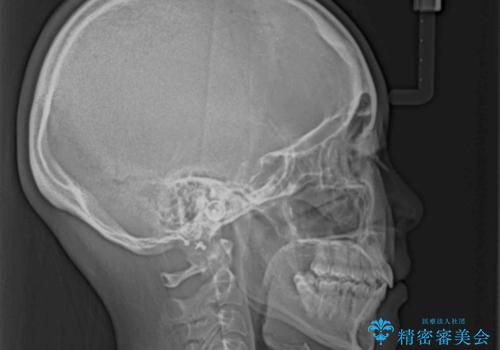

上下の咬み合わせは、下顎に対して上顎が相対的に前方にあったため、奥歯のシザーズバイト改善後に上顎左右第一小臼歯2本を抜歯し、上顎前突を改善していくこととしました。

左側の咬み合わせと上下正中の位置をコントロールするために時間がかかりましたが、事前に思い描いた通りの歯列に整い、患者様には大変満足していただきました。